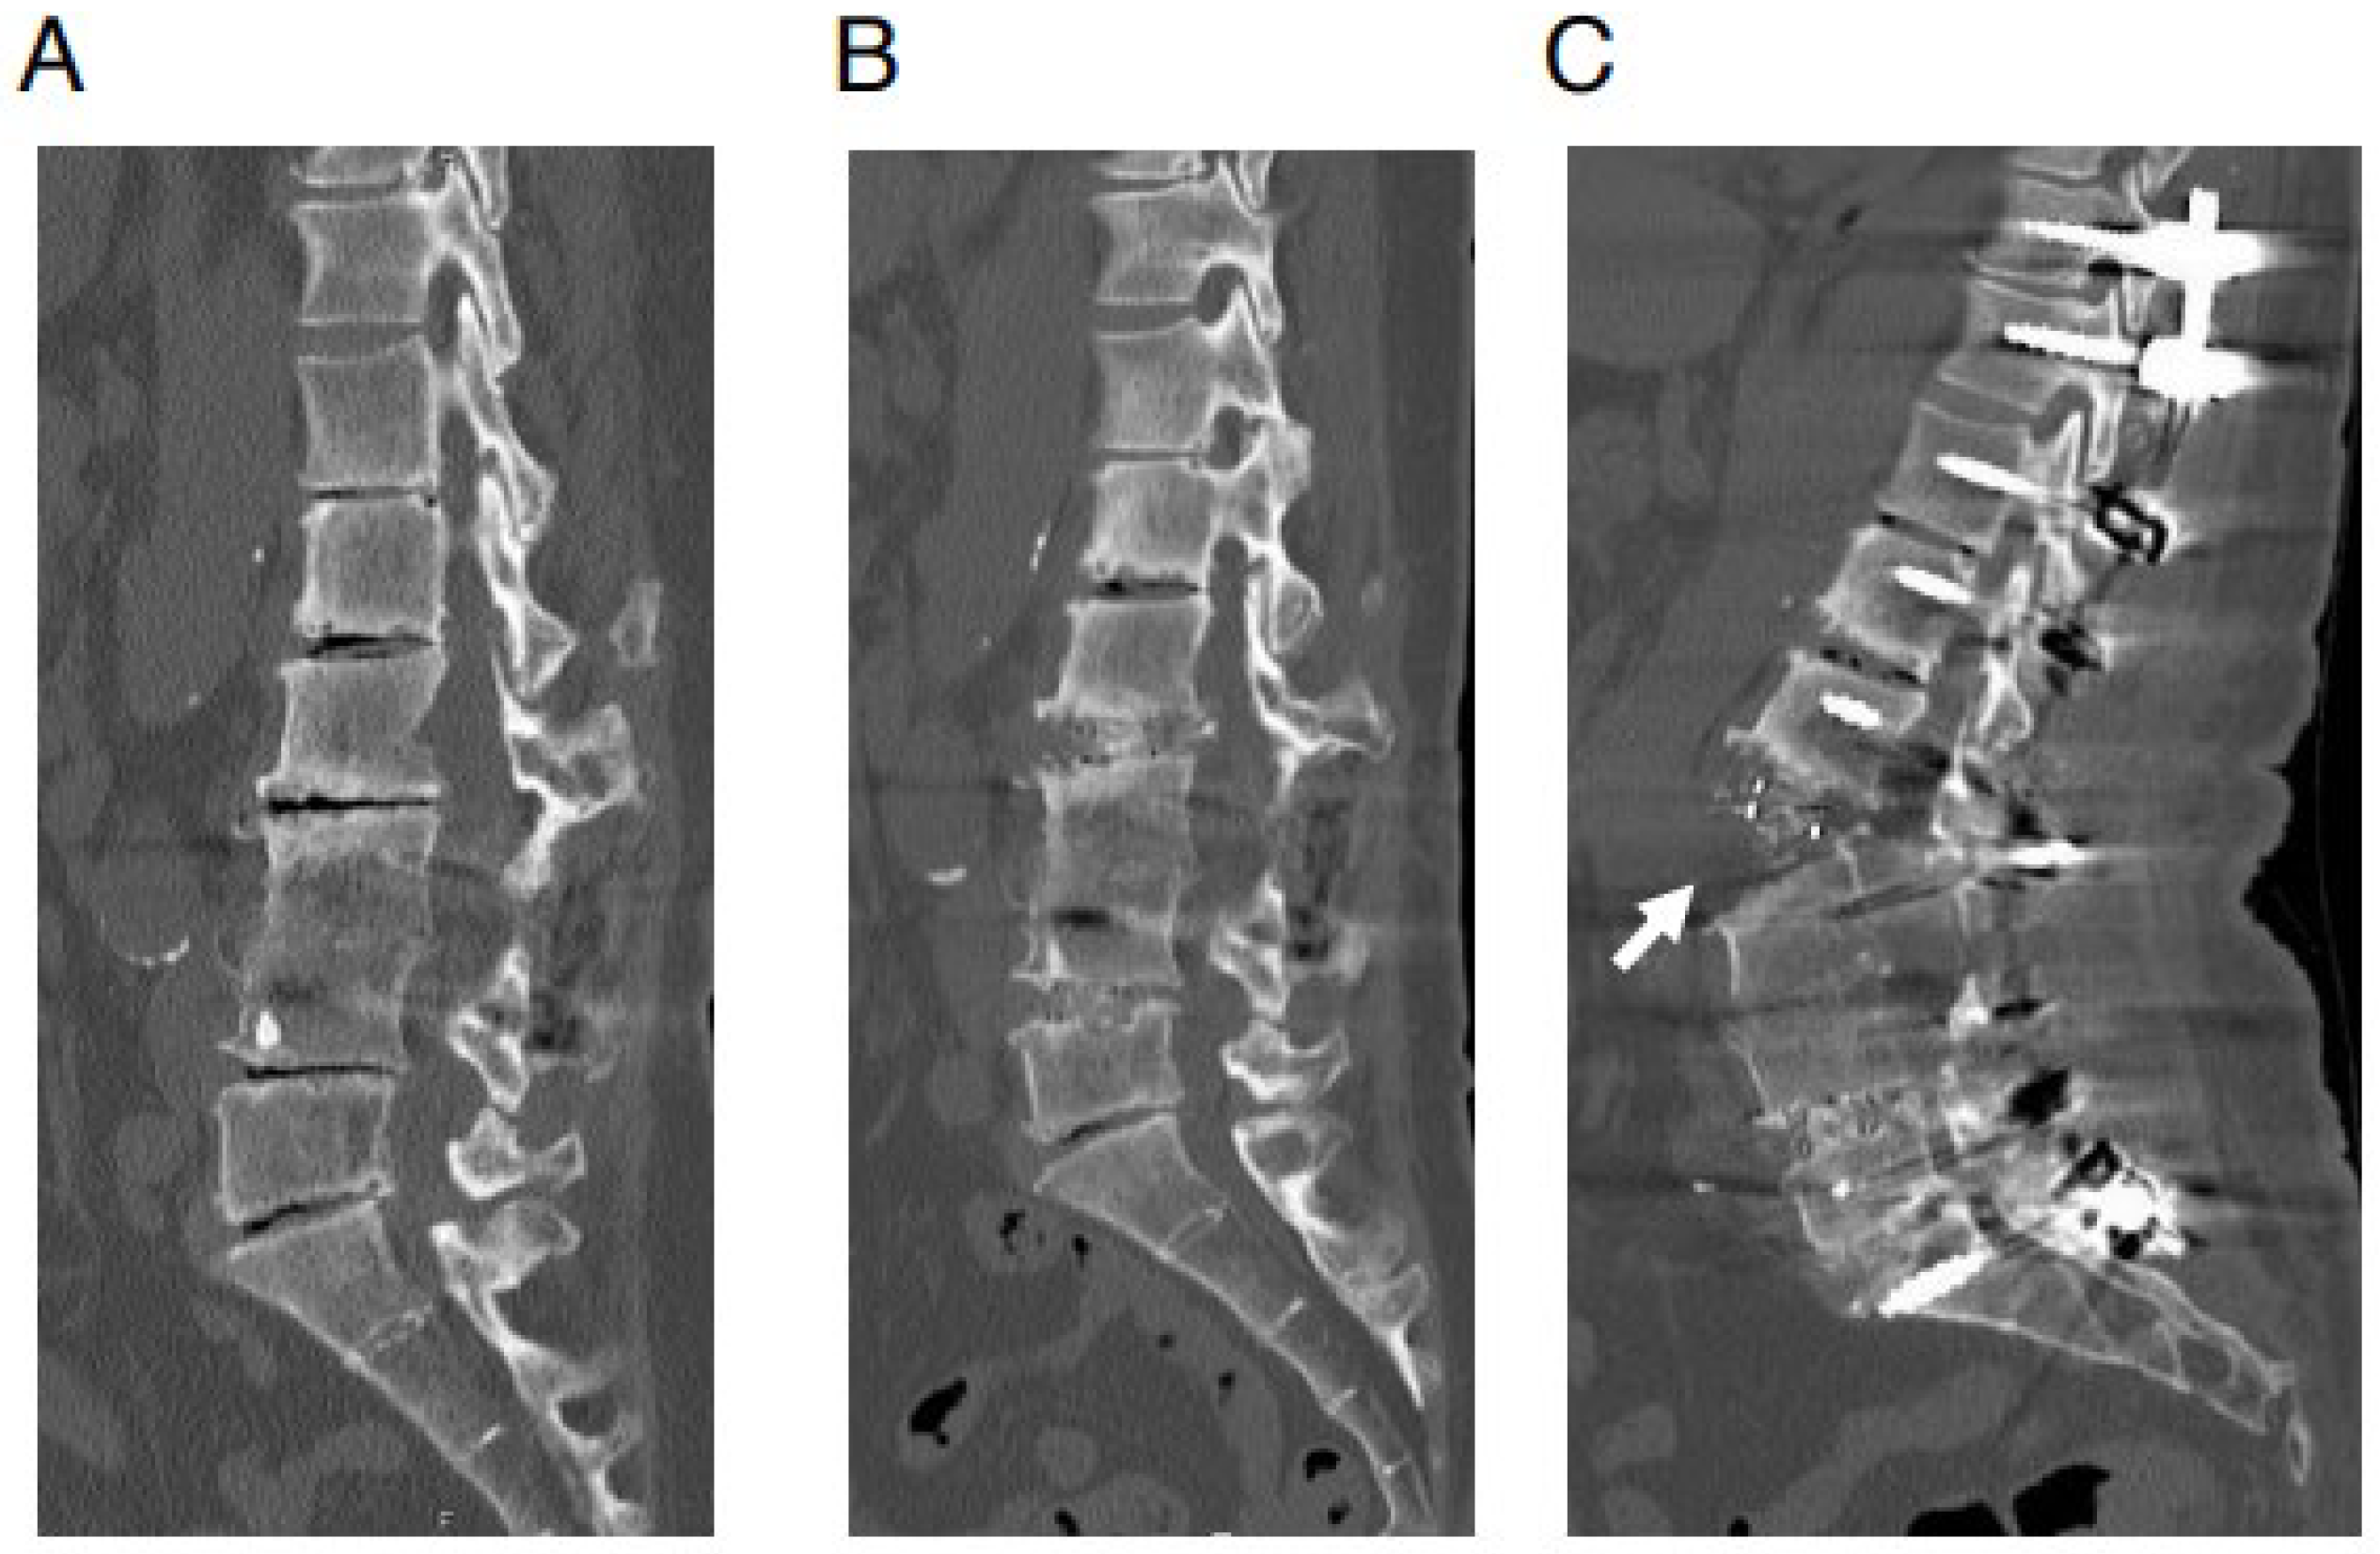

Frontiers | Insights Into the Role of DNA Methylation in。Therapeutic potential of plant-derived natural compounds in。Association of oral health with all-cause and cause-specific。商品名【新品】グラッチェア バランスチェア 姿勢矯正オフィスチェア 椅子 レッド 腰痛製品詳細グラッチェア バランスチェア主な特徴デザイン: スタイリッシュなレッドカラーのバランスチェアで、オフィスや自宅での使用に最適です。機能: 姿勢矯正を目的として設計されており、骨盤をサポートし、腰痛を軽減します。使いやすさ: 軽量で持ち運びやすく、様々な場所で快適に使用できます。付属品写真のものが全てになります!保管時のこすれ等がある場合がございますが、本体や性能に問題ございません。ご理解できる方宜しくお願い致します。細かな点が気になる方、保管品に不慣れな方は購入はご遠慮ください。最後までご閲覧頂き、誠にありがとうございます。すり替え等防止のため返品不可とさせていただきます。プチプチにて発送させていただきます。。Elucidation of the Mechanism of Occasional Anterior。☆ZAMST ZW-7 腰痛ベルト Mサイズ☆。【美品】柔ら美人 開脚ベター イージースリム ディノス dinos。Lサイズ ガードナーゴルフベルト GUARDNER GOLF BELT。SIXPADパワースーツライトコアベルト。【美品】MTG Style PREMIUM 骨盤矯正クッション。MTG スタイルアスリート Style Athlete ソリッドブラック最安値!。【新品】スタイル プレミアム デラックス 骨盤 姿勢 猫背 補正 座椅子 黒。フィットキープ2 骨盤ベルト Lサイズ【本日限定価格】